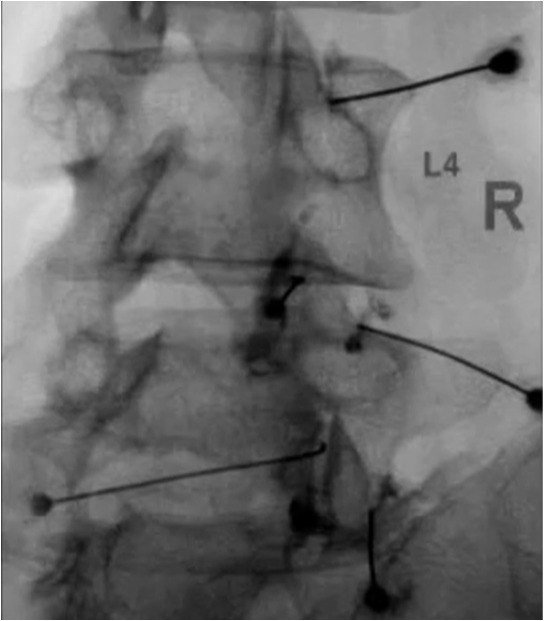

- Epidural steroid injections

- Selective nerve root blocks

- Facet or ligament-targeted injections